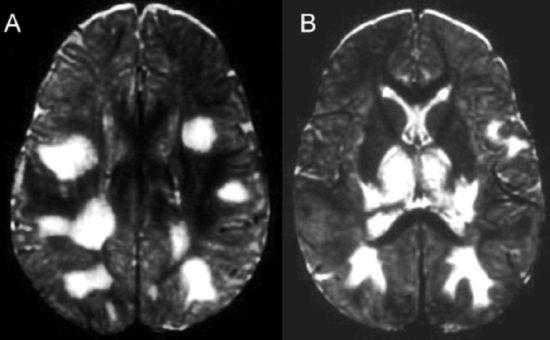

При МРТ выявляются множественные очаги, гиперинтенсивные на Т2-зависимых томограммах, со слабым отеком вокруг них.

Типичная локализация - белое вещество перивентрикулярных зон, области водопровода, стык коры и белого вещества, базальные ганглии. Последнее отличает токсоплазмоз от цитомегаловируса, который не вовлекает подкорковые ядра.

Очаги могут быть неоднородными за счет кальцификации, реже кровоизлияний в очаг. Контрастирование хорошее, по кольцевому типу, реже узловому. Учитывая, что токсоплазмоз легко принять за лимфому, нередко практикуют пробный курс приема противопаразитарных препаратов. Очаги токсоплазмоза уменьшаются в течение 1-2 недель, в то время как лимфома остается без изменения.

Цитомегаловирусная инфекция приводит к энцефалиту и вентрикулиту. Очаги двухсторонние с характерной локализацией в полуовальных центрах. Вентрикулит виден при контрастировании гадолинием как усиление стенок желудочков.